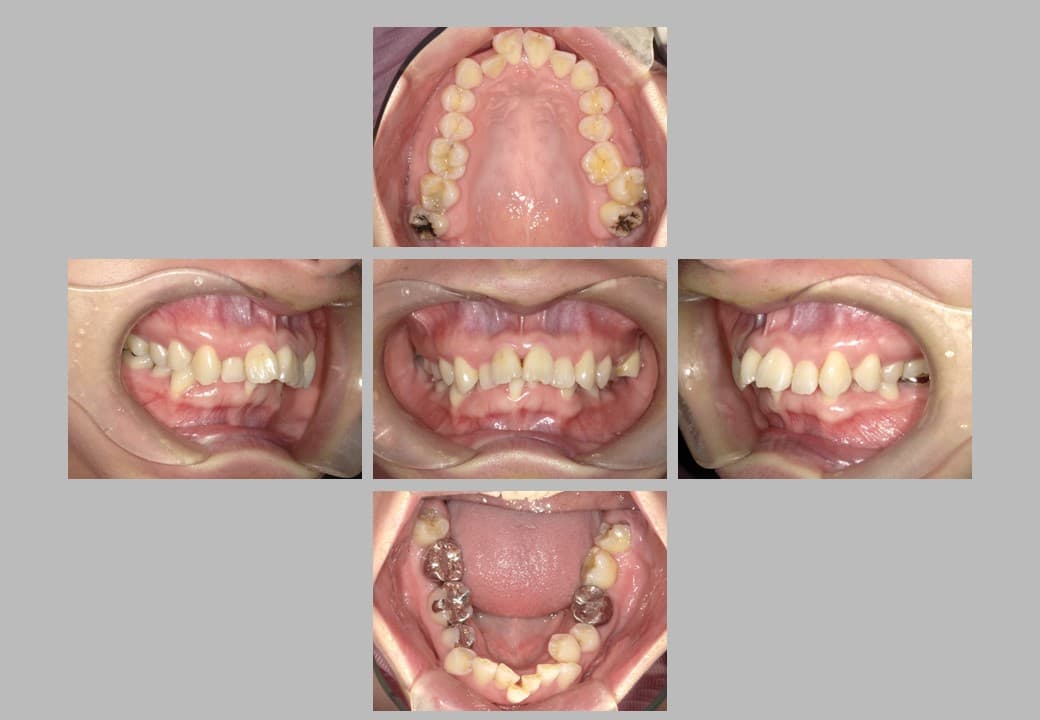

• 治療前